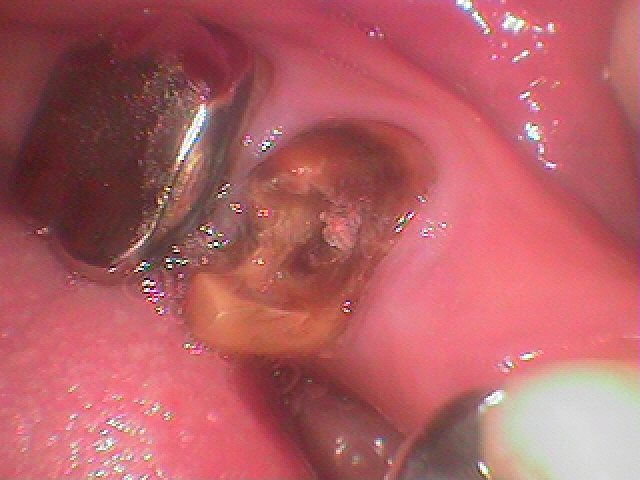

左下の奥歯のインプラント埋入|お知らせ |広島市安佐南区の歯科医院 左下の奥歯のインプラント埋入 トップ お知らせ・ブログ お知らせ 左下の奥歯のインプラント埋入 左下の奥歯のインプラント埋入 左下の6番ヘミセクション このクラウンが揺れてきました 骨吸収が認められます 割れているため抜歯となりました 抜歯しました 埋入していきました 補填材を入れ縫合して終了です このように埋入しています Web診療予約 初めての方へ 選ばれ続ける理由 院内設備について 歯が痛いしみる一般歯科 歯がぐらぐらする歯周病 健康な歯を保ちたい予防歯科 子供の虫歯予防をしたい小児歯科 銀歯をセラミックに審美歯科 白い歯を目指しませんか?ホワイトニング 矯正専門医がいるので安心矯正歯科 抜けた歯を補いたいインプラント・入れ歯 医院案内 スタッフ紹介 メリィハウス歯科クリニックオフィシャルホームページ ラベンダー歯科クリニックオフィシャルホームページ お知らせ・ブログ ホーム 診療科目 一般歯科 歯周病治療 予防治療 小児歯科 審美治療 ホワイトニング 矯正歯科 入れ歯・インプラント マウスピース矯正 初めての方へ 院長・スタッフ 設備紹介 医院案内・アクセス メニューを閉じる